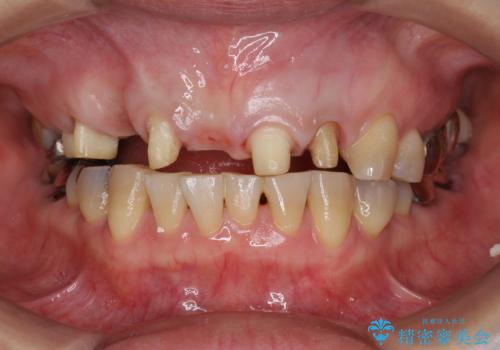

- 前歯を噛みしめにより失い、さらに犬歯もグラグラになり全く噛めなくなり改善を求めて来院されました。

過度な力がかかり周囲の骨に高度な吸収が見られた犬歯は抜歯し、機能・審美性の回復をより咬合力に対して抵抗力のあるブリッジ補綴にて対応します。